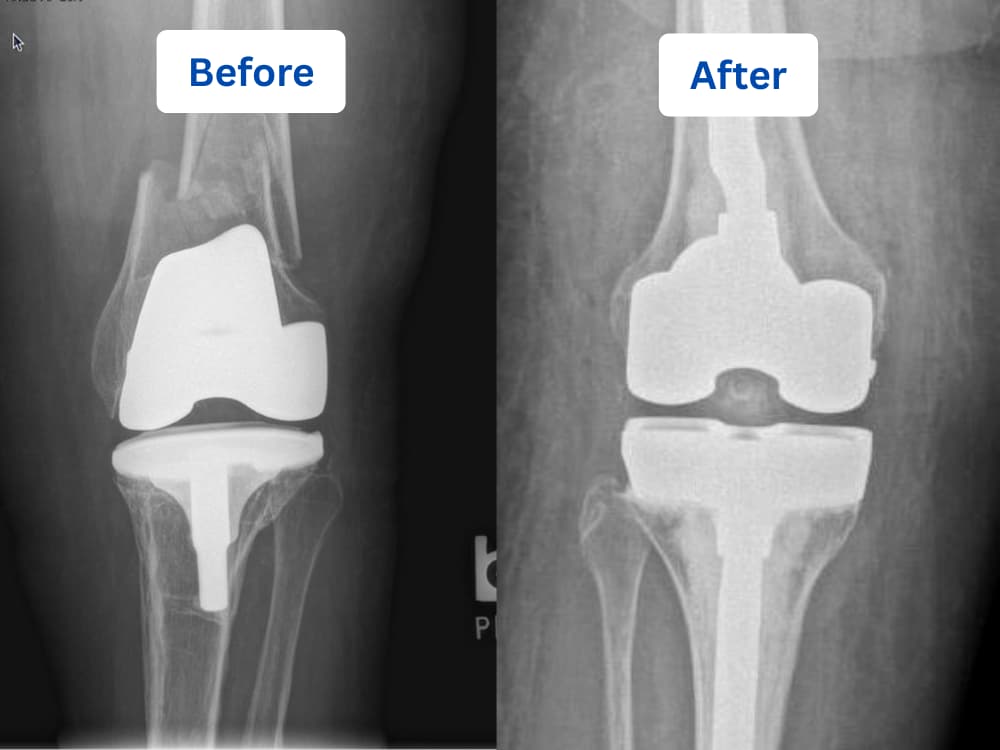

Unlike primary knee replacement, revision surgery involves carefully removing the old implant, treating damaged bone and surrounding tissues, and reconstructing the knee using advanced surgical techniques. Specialized titanium components and high-performance joint surfaces are then precisely positioned, sometimes supported by bone grafts, to restore stability, alignment, and smooth pain-free movement.

Revision knee replacement requires specialized implant systems designed to manage bone loss, instability, fractures, and previous implant failure. The choice of implant depends on the cause of revision, bone condition, and overall joint stability. At Dr. Tarabichi’s Center for Joint Care, we provide a full range of advanced revision solutions to meet each patient’s specific needs.

The revision knee implant systems include:

Modular Revision Knee Systems:

Designed to replace failed implants and restore joint alignment and stability. These systems allow flexibility in sizing and configuration to adapt to complex revision cases.

Cones and Augments Systems:

Used to rebuild bone loss caused by fractures, loosening, or previous surgeries. These specialized components provide strong structural support for the new implant.

Rotating Hinge Knee Implant System:

This advanced revision implant is used in complex cases where the knee has severe instability, major ligament damage, significant bone loss, or fractures around the joint. The rotating hinge design connects the thigh bone (femur) and shin bone (tibia) with a secure mechanical hinge that allows controlled bending while still permitting natural rotational movement.

During these visits, a clinical examination is conducted to assess the patient’s progress. The patient is questioned about their activities, such as walking, climbing stairs, sitting on the floor, and other daily tasks. X-rays are also taken to ensure that the new joint is functioning properly.